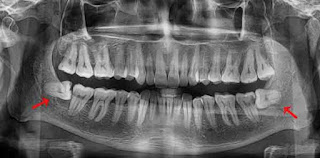

| Răng khôn mọc nằm ngang* |

Do mọc sau cùng, khi răng và xương hàm đã phát triển ổn định nên sẽ không còn đủ chỗ để răng khôn mọc bình thường. Lúc này, chúng sẽ mọc lệch, mọc ngầm, chen chúc nhau mọc gây ra nhiều ảnh hưởng đến sức khỏe. Có nhiều trường hợp răng khôn mọc ngầm, mọc lệch không can thiệp kịp thời, khiến phần nướu răng sưng tấy, dễ tích đọng thức ăn gây hôi miệng, viêm nướu...